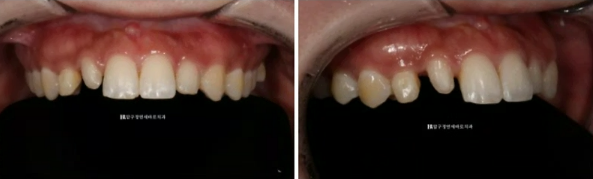

23.02

첫날 측절치의 레진을 제거한 모습입니다. 레진을 제거하고 나니 좌우 남는 공간이나 위치가 많이 다르네요 이 상태에서 무삭제 라미네이트 사이즈가 좌우 같게 제작되기는 어렵습니다.

또 지금처럼 윗니가 아랫니를 덮지 않고 끝과 끝이 일자로 만나는 절단교합 상태에서는 라미네이트 치료 후 깨지거나 떨어지거나 교합 불편감이 생깁니다.

앞니에 절단교합이나 반대교합이 있다면 몇 개월 단기 앞니 교정으로 교합을 좋게 만든 후에나 무삭제 라미네이트가 가능합니다.

이 분도 라미네이트 치료에 앞서 앞니 부분교정을 먼저 하고 하는 김에 아랫니 벌어진 부분 개방교합도 함께 해결하기로 했습니다.

교정 시작 7개월째 교정장치를 제거한

삭제 없이 라미네이트가 들어간 모습입니다.

가운데 앞니 두개는 본래 치아이고 파란 화살표 부분만 무삭제 라미네이트입니다.